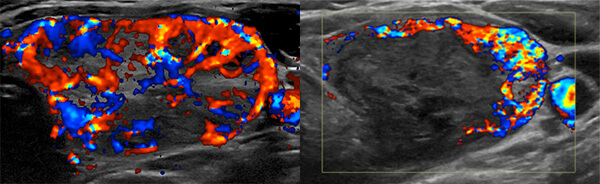

Radiofrequency ablation (RFA) is a minimally invasive method of shrinking tumors using heat energy to destroy tissue. It has been applied by Interventional Radiologists under real-time image-guidance for many decades to treat cancers in the lung, liver, and kidney as an alternative to invasive surgical resections. RFA of the thyroid has been shown to be a safe and effective alternative to surgery to decrease size and improve symptoms associated with benign thyroid nodules.

RFA is suitable for patients with cosmetic concerns and/or symptoms associated with their benign thyroid nodules. Thyroid nodules that are solid (or predominantly solid) and proven to be benign following biopsy are appropriate for RFA. Hyperfunctioning thyroid nodules can also be appropriate for RFA.